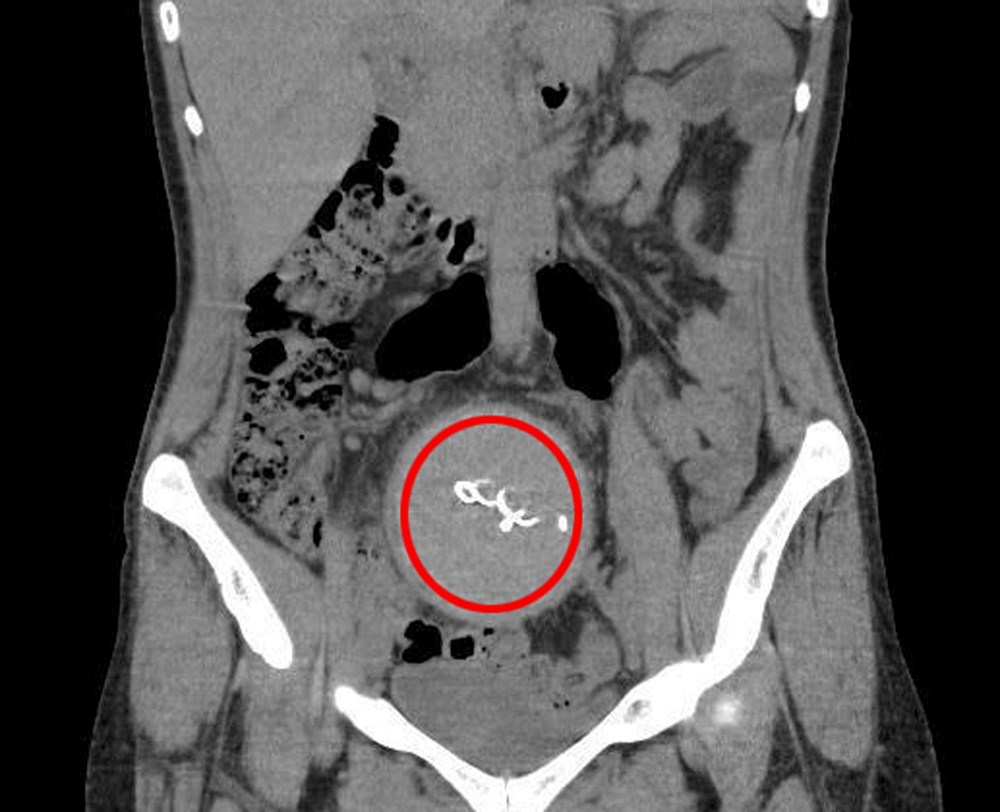

2023 yılının Ağustos ayında çekilen tomografide, Y.S.'nin vücudunda doğum sonrası unutulan sargı bezi görüldü.

Şoke olan Y.S., 2 yıldır yaşadığı ağrılara ihmalin sebep olduğunu öğrendi. Y.S.'nin karnında unutulan yaklaşık 30 santimetre uzunluğundaki gazlı bez ameliyatla alındı.